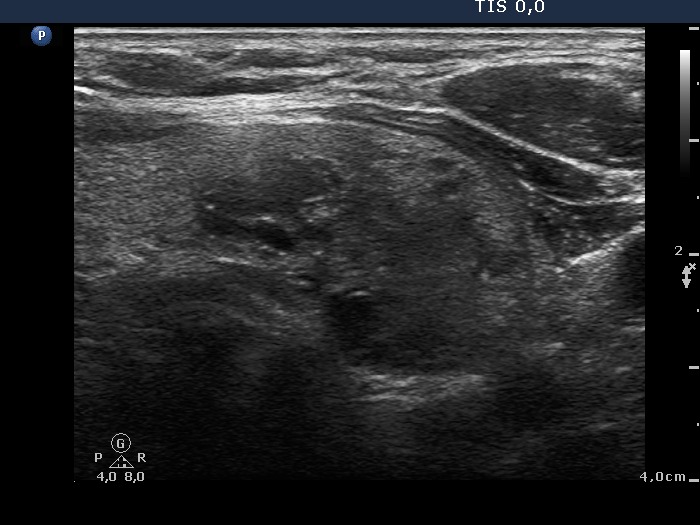

The borders of the nodule - case 186 |

Ultrasonography: The right thyroid contained a moderately hypoechogenic, the left had multiple nodules.

It is worth analyzing the nodule in the right lobe. At first sight it has spiculated margins, however thorough analysis reveals that the irregularity of the margin is caused by the impression of another nodule next to. There is a nodule having macrocalcification. The dorsal part of this lesion seems to be blurred, but this is caused only by the acoustic shadow.